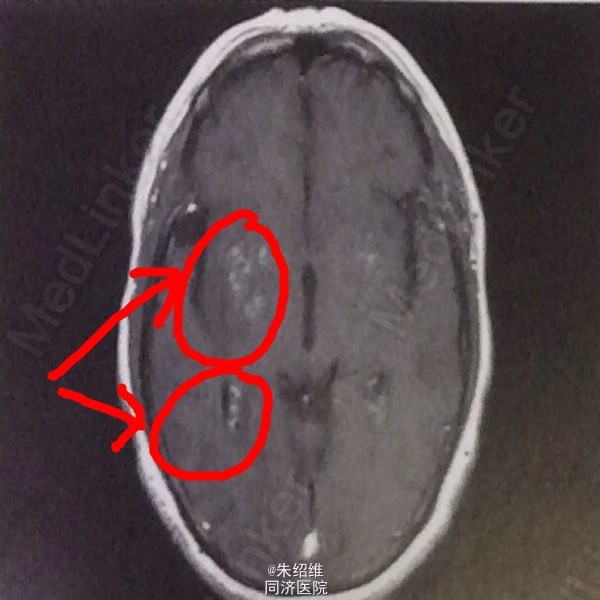

体检:脑膜刺激症阳性。MRI示两侧基底节区多发斑片状T1低信号,T2高信号,边界模糊,灶周水肿。增强病灶斑点状轻度强化。

诊断:双侧基底节区新型隐球菌脑病。给予抗真菌,降颅压治疗。